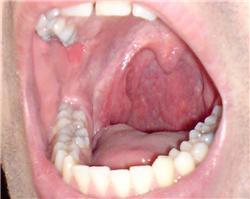

Pro větší náhled klikněte na obrázek

Dobrý deň, chcel by som sa spýtať ohľadom môjho dlhodobého problému s hrdlom a mandľami. Často som býval chorý kvôli hrdlu a neustále sa mi robil povlak na jazyku a mám neustále zápach z úst. Môžem si umývať zuby koľko chcem, ale aj tak za niekoľko minút začnšm cítiť, že mi páchne z úst. A antibiotiká mi vôbec nezaberajú. Horšie je, že som v anglicku, o tu doktori vravia, že je to ok, ale ja viem, že nie. Lebo na SK mi povedali, že mám akútny zápal mandlí, ale asi nezabrali ani tie naposledy antibiotika. Je najlepšie dať madle von? A na zadnej strane v hrdle mám nejaké opuchy, neviem ako sa to volá, ale vyzerá to ako hnisavé. Poraďte mi prosím Vás. Dakujem Marek

Ak ste Slovák kľudne píšte po slovensky ja vám rozumiem. Ďakujem. Ja vám ale skutočne nepomôžem. Môj názor na váš problém je taký, že ak je to také vážne a lekári vám navrhujú mandle dať von, keďže liečba je bezúspešná, tak je potom najlepšie ich dať von, je to jediné možné riešenie.